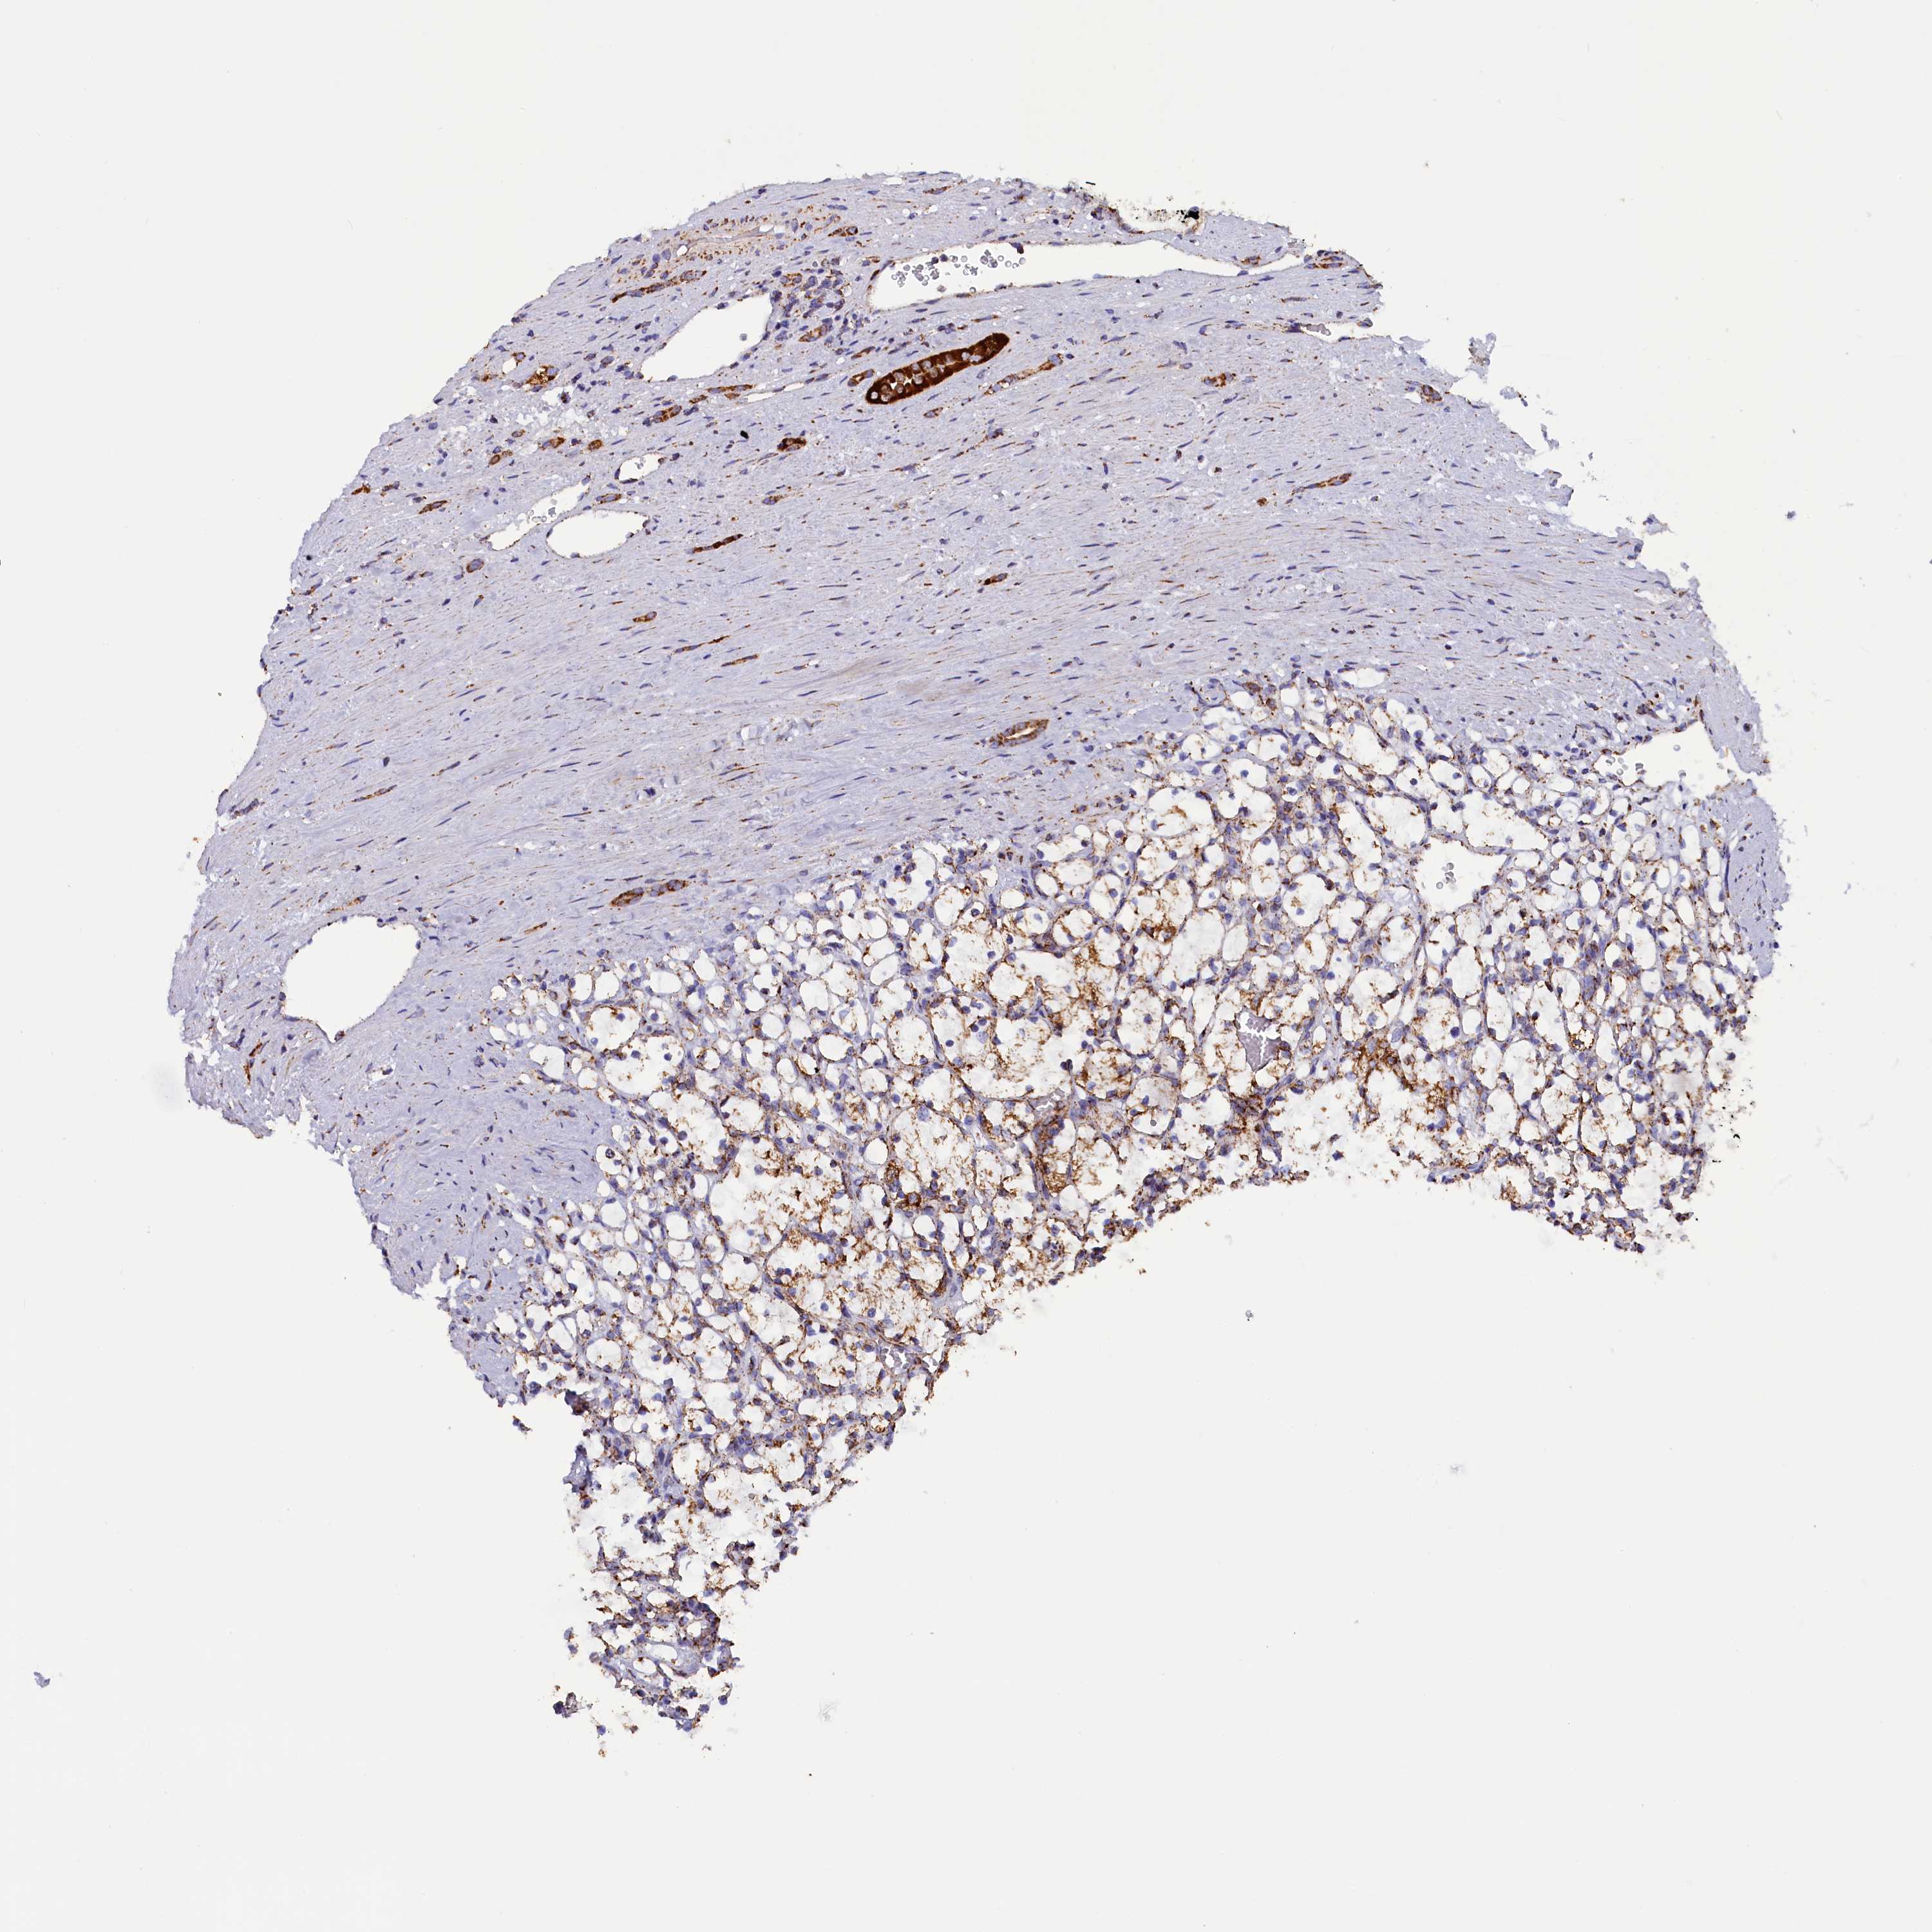

KIDNEY RENAL PAPILLARY CELL CARCINOMA (TCGA) - Interactive survival scatter ploti

The Survival Scatter plot shows the clinical status (i.e. dead or alive) for all individuals in the patient cohort, based on the same data that underlies the corresponding Kaplan-Meier plots. Patients that are alive at last time for follow-up are shown in blue and patients who have died during the study are shown in red.

The x-axis shows the expression levels (FPKM) of the investigated gene in the tumor tissue at the time of diagnosis. The y-axis shows the follow-up time after diagnosis (years). Both axes are complimented with kernel density curves demonstrating the data density over the axes. The top density plot shows the expression levels (FPKM) distribution among dead (red) and alive patients (blue). The right density plot shows the data density of the survived years of dead patients with high and low expression levels respectively, stratified using the cutoff indicated by the vertical dashed line through the Survival Scatter plot. This cutoff is automatically defined based on the FPKM cutoff that minimizes the p-score. The cutoff can be changed by dragging the vertical line or by entering a cutoff value in the square labeled "Current cut-off".

Under the Survival Scatter plot the p-score landscape (black curve; left axis) is shown together with dead median separation (red curve; right axis). Dead median separation is the difference in median mRNA expression between patients who have died with high and low expression, respectively. It is calculated as follows: median FPKM expression of dead patients with high expression - median FPKM expression of dead patients with low expression. This is intended to aid the user in visually exploring custom cutoffs and the associated p-scores and dead median separation.

Individual patient data is displayed and can be filtered by clicking on one or more of the category buttons on the top of the page. Categories describing expression level and patient information include: high, low, alive, dead, female, male and tumor stages. The scale of the x-axis can be toggled between linear and log-scale by clicking on the "x log" button. Mouse-over function shows TCGA ID, patient information and mRNA expression (FPKM) for each patient.

& Survival analysisi

Kaplan-Meier plots summarize results from analysis of correlation between mRNA expression level and patient survival. Patients were divided based on level of expression into one of the two groups "low" (under cut off) or "high" (over cut off). X-axis shows time for survival (years) and y-axis shows the probability of survival, where 1.0 corresponds to 100 percent.

SLC39A3 is not prognostic in Kidney Renal Papillary Cell Carcinoma (TCGA)

Best expression cut offi

Based on the FPKM value of each gene, patients were classified into two groups and association between prognosis (survival) and gene expression (FPKM) was examined. The best expression cut-off refers the FPKM value that yields maximal difference with regard to survival between the two groups at the lowest log-rank P-value. Best expression cut-off was selected based on survival analysis .

When clicking on this number, the vertical dashed line indicating cut-off, the interactive survival plot, and the Kaplan-Meier curve will be adjusted to show results based on the best expression cut-off.

: 27.55